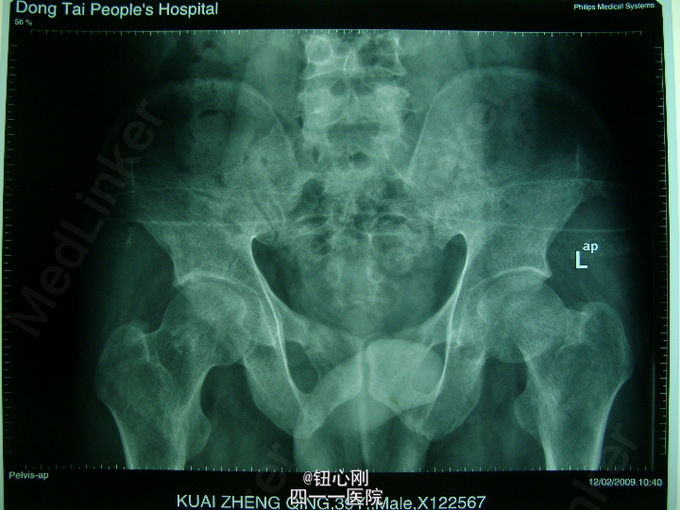

男,38岁,主诉全身多处骨关节疼痛5年。5年内身高降低5厘米,活动后全身关节疼痛加重,休息后减轻。疼痛以腰椎,全身大关节为主。既往体健,否认有肾功能不全及胃肠道病史,肝胆胰腺病史,无激素及其他特殊药物使用史。无毒物接触史。饮食正常,家族中无类似病史

查体间:略有驼背畸形,全身大关节及脊柱活动性降低,大关节处有明显叩压痛。 辅助检查:三大常规,肝肾功正常,血沉正常,各肿瘤指标正常,钙正常,血磷减低(0.44mmol/L),骨特异性碱性磷酸酶升高(99.95ng/L),PTH、CT正常,尿本周蛋白(-),血清蛋白电泳正常,无M蛋白,血皮质醇正常。 胸片,心电图,肝胆胰脾双肾B超正常。

病史特点:1、壮年男性,以全身多处骨痛为主,伴身高降低为主诉;2、体检可见:驼背畸形,脊柱及四肢大关节处活动降低,有叩压痛;3、辅助检查提示:血磷减低,血钙正常,影像学显示:全身骨骼骨质疏松改变,未见其它骨破坏。 鉴别诊断:排除骨髓瘤,转移性肿瘤,甲状旁腺亢进,肾性骨病,原发性及药物性骨质疏松 诊断:成人低磷性骨软化症 治疗:予以钙片、骨化三醇,中性磷酸盐口服